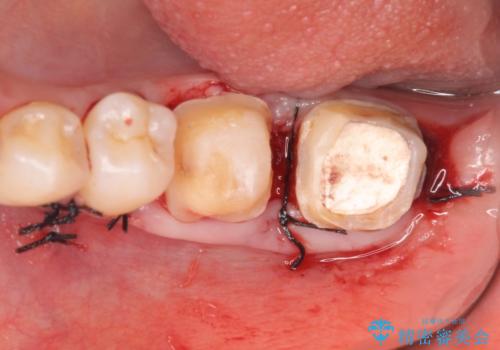

また左下6は遠心にあった歯茎より深い虫歯(縁下カリエス)の問題を解決するため、歯茎を下げる歯周外科手術を行いました。

歯周外科手術終了後、歯茎の回復を待ち左下6、7ともにオールセラミッククラウン(スタンダード)による補綴を行いました。